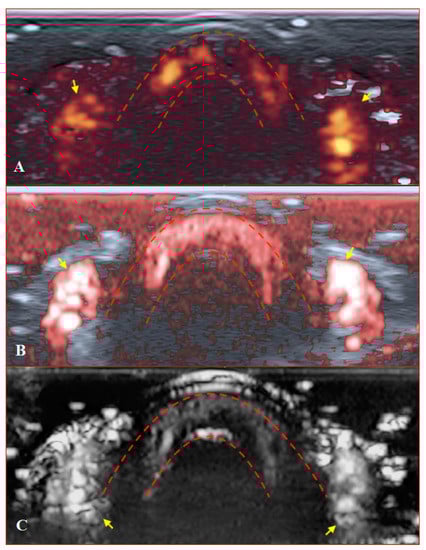

Figure 5. Ultrasound images of the nailfold of the fifth finger of the patient with a late course of SSc: (A1,A2) B mode/grayscale; yellow dotted lines mark the nail, red arrows mark the lateral nailfold, which is decreased due to sclerodactyly. (B1,B2) PD; there is an avascular zone in B2 in the deeper layers of the nailfold; B1 does not show any vascular sign with maximal gain. (C1,C2) cSMI; white arrows mark the true flow in the random noise background; the area marked by dotted lines in C2 is also avascular and the true flow signals on the sides show the lateral nailfold. (D1,D2) mSMI; confirms cSMI findings.

PD and SMI settings have to be standardised for all evaluations. There is an appropriate option to differentiate primary Raynaud’s syndrome from its secondary development by setting the gain. Martinoli et al. suggested increasing the gain maximally and then slowly lowering it until the noise disappears and true signals remain [20]. Rubin offered a converse way to raise the gain manually until the colour box becomes filled with signals and a true flow is distinguished from the background as the next highest signal [21]. The method by Rubin seems to be a quick and comfortable technique to check vascularity in fingertip pulp and nailfold zones (Figure 6 and Figure 7). It takes less time to evaluate vascularity by SMI modes rather than the conventional PD technique due to its higher sensitivity for low flow. Monochrome SMI is a comfortable mode for the evaluation of vasculature and even vascular torsions, as the true flow has more power, and it is easier to separate these dots from the background of random noise artefacts (Figure 4D2).

The difference between healthy and SSc-affected fingertips is obvious using Rubin’s method. Higher gain shows that there is no signal in PD and minimal dots with both SMI modes (Figure 5).